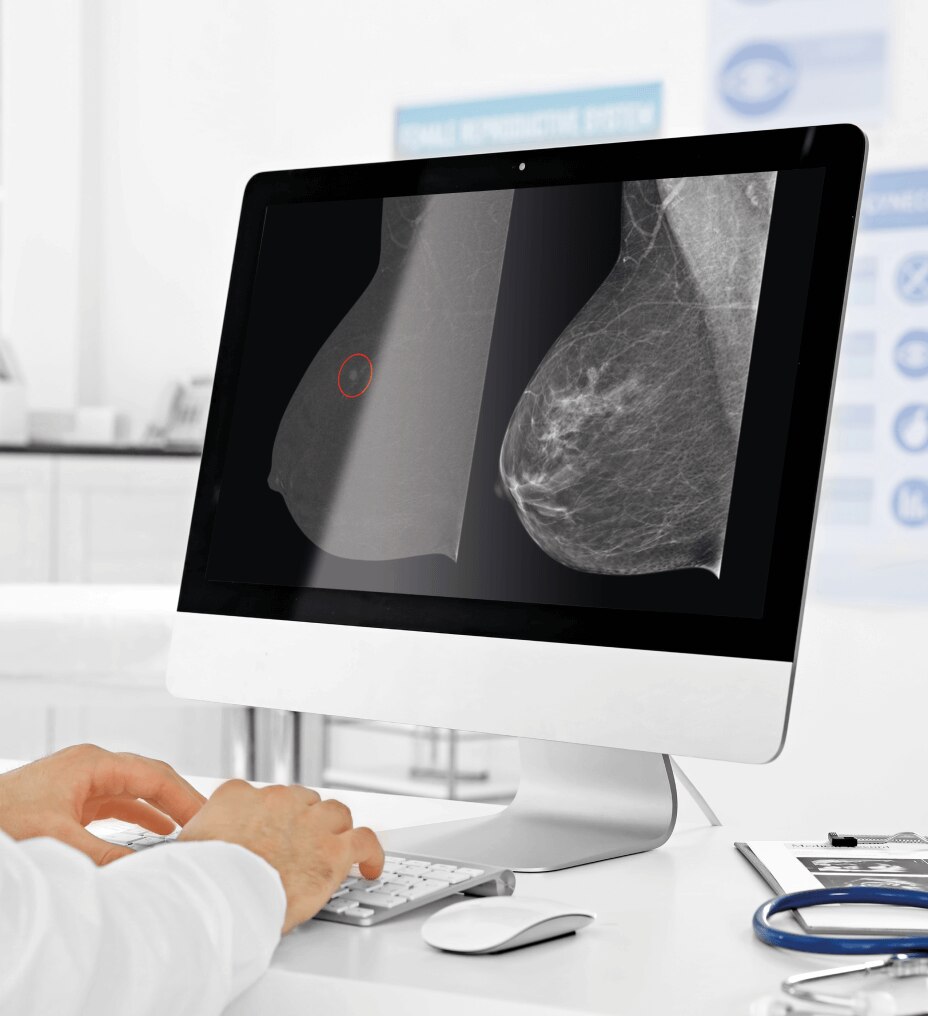

Vea los testimonios a continuación y descubra cómo estos médicos están utilizando Vscan Air en su práctica.